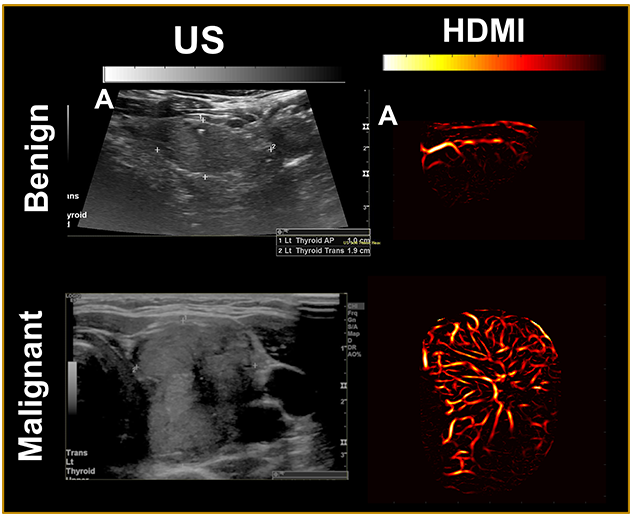

The method — deemed high-definition microvasculature imaging, or HDMI — noninvasively captures images of the tiny vessels within tumors and, based on the vessel features, automatically classifies the masses. Researchers at the Mayo Clinic College of Medicine and Science, who developed the technique, tested it on 92 patients with thyroid tumors, finding that the method could distinguish if the growths were cancerous with 89% accuracy. In a study published in the journal Cancers, the authors suggest that HDMI could potentially resolve a long-standing diagnostic challenge of assessing thyroid tumors in the clinic.

The researchers took pictures of the tumors with HDMI and measured a dozen features related to the size and shape of the microvasculature in the images, including their density and number of branching points.